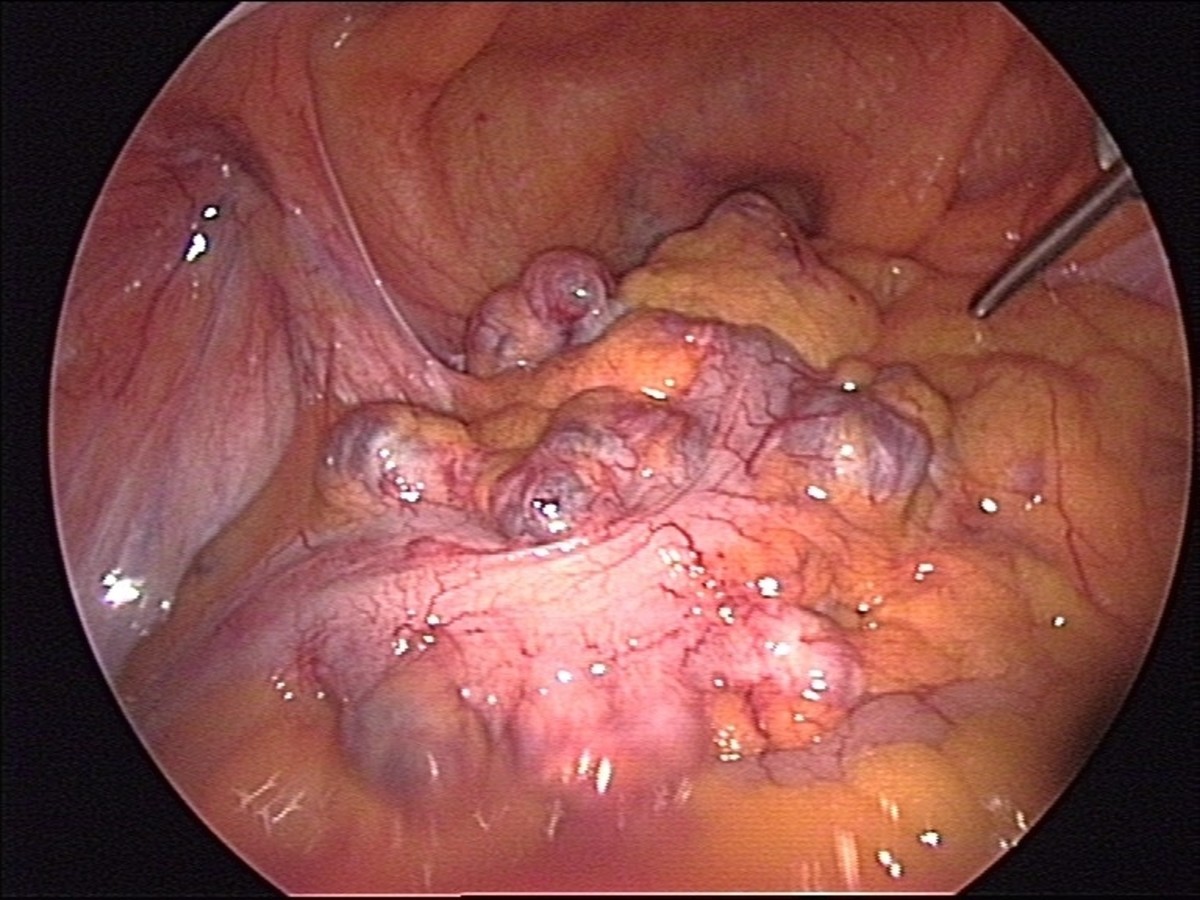

Diverticulosis is a condition in which tiny little holes in the intestinal wall enlarge, forming sacs, or diverticula, that can range from the size of a pea to the size of a penny. 10% of the American public over 40 have diverticulosis—some with extreme symptoms. 50–60% of Americans over 60 deal with it.

When the sacs push through the softer outer layer of the intestines, it is referred to as a herniated diverticulum. These sacks can retain fecal material, leading to inflammation and infection. When infected, the condition is known as diverticulitis.

An Inside Look at Diverticulosis

Click thumbnail to view full-size